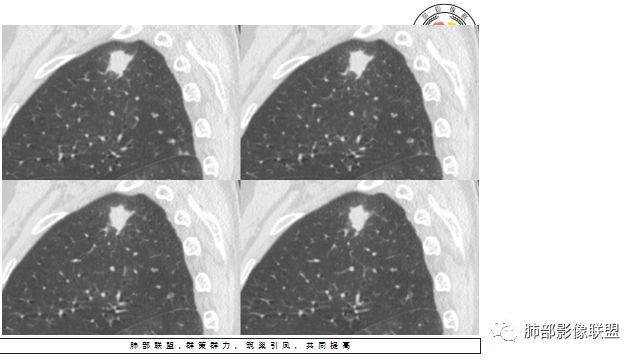

胸CT:右上肺结节,病灶位于胸膜下,边缘可见平直 u型征 软毛刺 晕,增强可见延迟强化,病灶中心低密度区。

2.右肺尖类圆形结节影,边界清楚,未见明显分叶或深切迹,部分分边缘较平直,可见细长毛刺棘状突起,相邻胸膜增厚,未见胸膜凹陷。后段胸膜下见条索影及微小结节影。

相关血管未见脐凹,有限图像层面未能显示相关支气管情况。

3.平扫病灶密度密度不甚均匀,外侧份见微小高密度影。

4.增强扫描成明显环形强化,中央液化坏死,内壁清楚且较为规整。